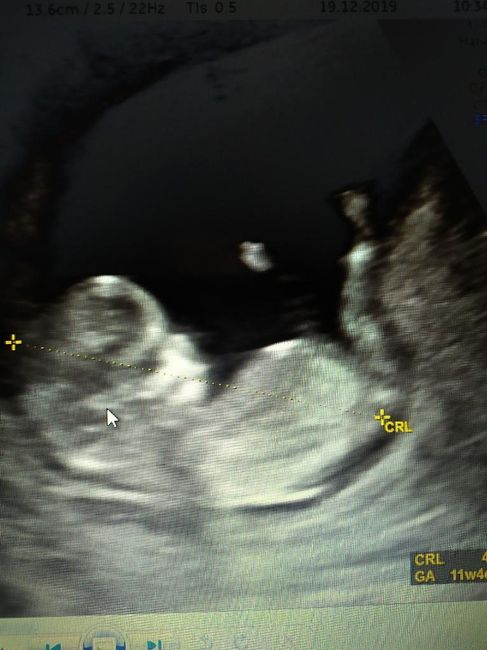

Ciao a tutte!!noi stiamo impazzendo nell'attesa del sesso del mio scricciolo.. secondo voi cos'è? semplice curiosità.. 😊😊